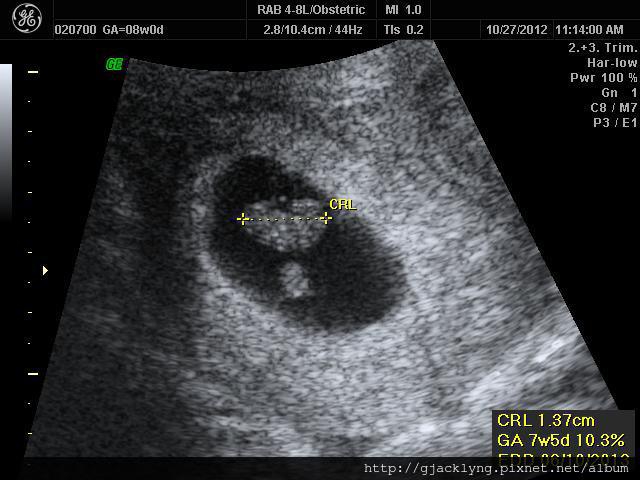

10/27(8W1D)

我來到林聖凱婦產科要照寶寶心跳了

寶寶很好....也有了心跳

林醫師當天也發了媽媽手冊給我

一切都跟我預期的一模一樣

(我害喜成這樣....寶寶如果還不健康就真的太太太過份了!!!)

照完超音波....

我跟林醫師提到了我悲慘的頭暈跟嘔吐